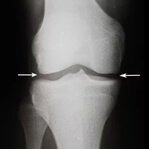

Artrita este inflamația articulațiilor, însoțită de durere puternică și mobilitate limitată. Conform statisticilor, 37% dintre persoanele cu artrită devin invalide dacă nu încep tratamentul la timp. Nu ignora semnele timpurii ale bolii!

Osteoartrita distruge treptat țesutul cartilaginos și duce la deformarea articulațiilor. În timp, chiar și cele mai simple mișcări devin imposibile, iar durerea devine constantă. O terapie corectă ajută la încetinirea progresiei bolii.

Umflăturile și inflamațiile genunchilor avertizează asupra unor probleme serioase. Fără tratament, acestea pot duce la pierderea completă a mobilității și chiar la necesitatea unei operații. Acționează imediat la primele simptome!